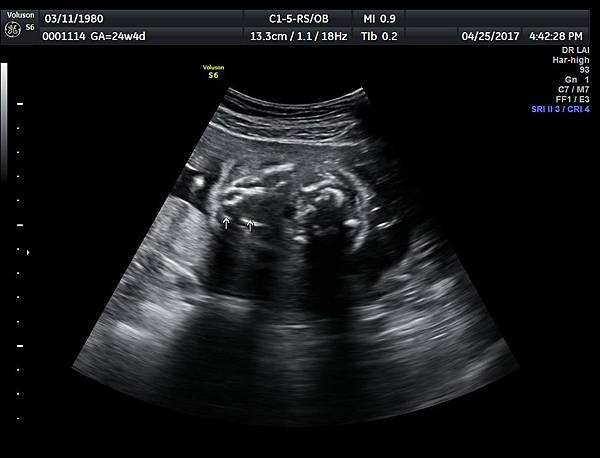

一個檢查如果要花很長的時間才能完成,這樣的檢查無法變成常規的篩檢方式,我已經在我的診所執行懸雍垂檢查一段時間,我檢查懸雍垂大約30 秒,前提是胎兒的臉最佳位置是側躺,其次是側躺偏向上,我的檢查步驟是上顎(含日後大門牙長出的位置)、舌頭、懸雍垂(= equal sign)(附圖1~8),如果超過60秒無法完成,只有兩個原因,一個是胎兒姿勢不適合或喉嚨羊水空間太小,這時候不要硬碰硬,只要先檢查其他部位,等待時機再回來即可,我的經驗是90%的cases都能順利完成這項檢查(肚皮厚的case真的是很難)。